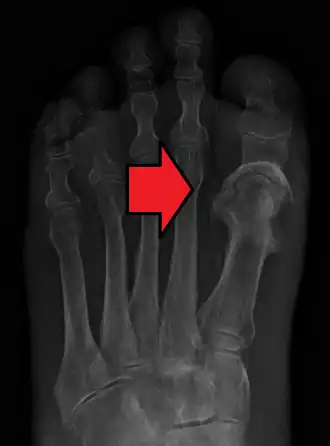

Osteomielite no hálux